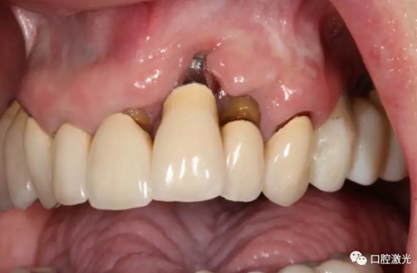

激光非手術(shù)種周炎治療前與治療后2年的對比